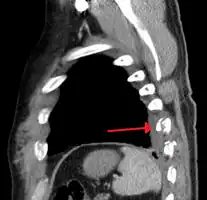

矢狀面的電腦斷層影像顯示有兩根肋骨骨折

照X光可確定位移性骨折,但是往往容易忽略無位移的骨折[13];以電腦斷層檢查可確定這兩種骨折[13]。 因為兒童的肋骨較成人有彈性,所以較可能彎曲而非直接折斷,因此當兒童患者發生肋骨骨折,代表其遭受劇烈的撞擊,同時也表示患者胸部很可能有重大傷害,如發生肺部挫傷[4]。年長者會發生肋骨骨折,也表示曾遭受較嚴重的外傷[14]。